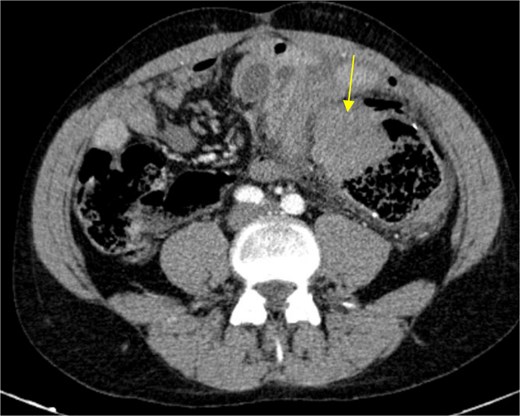

The patient presented at our Emergency Department with a sudden, diffuse, intense abdominal pain. Upon physical examination, the patient’s blood pressure was measured at 132/76 mmHg, heart rate of 103 bpm and a temperature of 39.4°C. The abdominal examination showed a rigid abdomen, with diffuse tenderness, suggesting an acute abdomen scenario. Laboratory tests revealed elevated inflammatory parameters. A abdominal and pelvic computed tomography scan revealed pneumoperitoneum and free fluid in the right iliac fossa and pelvis (Fig. 1). An exploratory laparotomy was proposed and the intraoperative findings included a sigmoid colon perforation with faecal peritonitis. They proceed with sigmoidectomy and temporary abdominal closure, planning for a reintervention to restore gastrointestinal continuity. This was done, after 48 h, through mechanical latero-lateral colo-colic anastomosis. The histopathological examination confirmed diverticulosis with perforation. The patient was subsequently transferred to the intensive care unit, for 5 days. Posteriorly, he developed severe left lumbar pain and hypertension unresponsive to medication. A CT scan revealed left kidney acute ischemia due to left renal artery thrombosis (Fig. 2). Broad-spectrum antibiotic therapy and anticoagulation, was initiated, after assessment by the Vascular Surgery and Urology teams. During his hospitalization, the patient experienced additional thrombotic events, such as occlusion of the left radial artery, and right lower lobar pulmonary embolism. A workup for prothrombotic conditions was conducted, including tests for thrombophilia, lupus, cardiolipins, antinuclear antibody, total protein test, and immunoglobulins, all of which were negative. An angiography of the abdominal aorta revealed arterial microaneurysms in the splanchnic territories: hepatic, perigastric and mesenteric arteries, suggesting polyarteritis nodosa (Fig. 3). Echocardiogram showed no abnormalities. The patient also underwent a study of the left shoulder due to repetitive pain complaints, with a suspected rupture of the rotator cuff. Electromyography excluded peripheral nerve damage. No other complications were reported. The patient was discharged on the 21st day after surgery, under anticoagulation therapy and steroids due to a suspected diagnosis of polyarteritis nodosa. Twenty-seven days after surgical intervention, the patient returned to the ED, presenting with abdominal pain in the lower quadrants and nausea. He was hemodynamically stable with abdominal pain and tenderness on the left flank and iliac fossa. Laboratory tests revealed leukocytosis and hyperlactacidemia. The CT scan reported free fluid, free gas bubbles adjacent to the sigmoid which had a concentric circular thickening of the wall, just distal to the previous anastomosis (Fig. 4). An exploratory laparotomy was performed, during which a large hematoma on the wall of the left colon was identified, with no apparent signs of perforation. A peritoneal lavage, drainage, and a derivative ileostomy were carried out. During the post-operative period the patient maintained a small volume of purulent discharge through the abdominal drain, with no abdominal tenderness. A reevaluation CT scan was performed, highlighting a regression of the hematoma of the colonic wall but raised suspicion of a low output fistula near the anastomosis. Since the patient maintained hemodynamic and analytical stability, he was discharged from the hospital with home care, including an abdominal drain, parenteral nutrition, empirical antibiotic therapy, and gradual reduction in the steroid dosage. The patient was referred to the ED, on Day 6, due to enteric drainage. An enterocutaneous fistula was diagnosed, and he was readmitted. He received 12 days of full-dose parenteral nutrition, which reduced the fistula output and improved his clinical and analytical status. Due to residual drainage volume and an analytical and imagiologic improvement, the drain was removed, and the patient was discharged, tolerating an oral diet, and with a functioning ileostomy.

Angiography of the abdominal aorta revealed arterial microaneurysms suggesting polyarteritis nodosa (arrows).